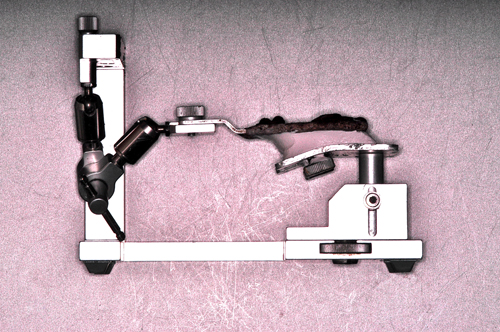

Palabras Clave: ELG: Estereolitográfico OH: Oclusión Habitual ORC: Oclusión en Relación Céntrica Paciente de 35 años de edad ,sexo masculino que lo derivan para implantar el tercer cuadrante. A la auscultación presenta ruidos articulares de tipo chasquido que remiten temporalmente luego de limitación de apertura bucal y maniobras quinesiológicas distractoras. También se observan recidivas de caries en algunos empastes y falta de disclusión canina de ambos lados. Se estudia el caso desde un punto de vista clínico, scanografico mediante Dentascan y tridimensional mediante montaje en articulador. A partir del scanner se obtienen datos para confeccionar modelo estereolitográfico (ELG),operar en el y construir férula quirúrgica dento-muco soportada. Habitualmente se procede directamente a implantar, dado que ese era el requerimiento del profesional derivante y el deseo del enfermo. Sin embargo, esa actitud enmascararía otro tipo de problemas que la boca presenta. Se consulta al odontólogo derivante, y coincide con mi opinión acerca de que si solo se lo implanta, sin corregir la posición mandibular, la situación de las ATMs, los empastes sin anatomía y la falta de disclusiones, el resultado final no será el deseado y su eficacia masticatoria no funcionará optimamente. Consultado el paciente coincide y acepta ese concepto y entonces procedemos a confeccionar un Jig de Lucia a partir del montaje de estudio, y lo dejamos puesto en boca toda la noche anterior a la consulta, para proceder a realizar un ajuste oclusal al día siguiente sin engramas anteriores, lo que facilita no tener que relajar nuevamente con laminillas de Long. En esta etapa pierde el implante correspondiente a la pieza 4.7 que traía en boca. Estabilizado el sistema, procedemos a la parte quirúrgica, comenzando por instalar la férula, retirar opérculos gingivales mediante bisturí circular, fresado óseo e instalación de implantes ,toma de impresión a cubeta fenestrada (pegando con metacrilato sin cambios dimensionales, los transfers a la cubeta especialmente diseñada.(1º método de pasividad protética utilizado), e instalación de tornillos de cicatrización. Inmediatamente de retirada la cubeta de boca y colocadas las réplicas de los implantes, procedemos a ferulizar los “ápices” de las réplicas para que no sufran movimientos durante el llenado de la impresión.(2º método de pasividad protética utilizado). Controlamos radiograficamente Tres meses después, procedemos a tomar nuevos registros de arco facial, registros intermaxilares en Oclusión en Relación céntrica, montaje de los modelos obtenidos intra operatoriamente y confección de un conjunto de cuatro coronas provisionales de metacrilato en el sector implantado y las correspondientes al maxilar superior. Verificada la perfecta función de todos los componentes, ausencia de todo tipo de síntoma y comprobada la paz en todo el sistema, procedemos tiempo después a confeccionar las fundas definitivas, que constituyen el “cerrojo” de la dinámica del mismo. Por último, corroboramos la oclusión fundamentalmente en lo que hace a la: